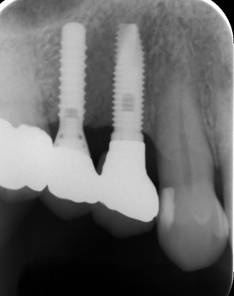

ストローマンインプラントとスプラインインプラント

術前

ストローマンインプラントとスプラインインプラントが隣り合わせに埋入されています.このころストローマンからスプラインに変えています。変えた理由は前歯部の審美性に優れていること、アバットメントの自由度があること、抜歯後すぐに埋入できるなどでした。